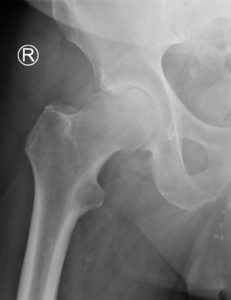

Hüfte

Nach dem Kniegelenk ist das Hüftgelenk das zweitgrösste Gelenk des Menschen. Als so genanntes Nussgelenk, eine Form des Kugelgelenkes, wird es vom Kopf des Oberschenkelknochens und der Pfanne im Becken gebildet. Unterstützt wird es durch eine Vielzahl von muskulären und bandhaften Strukturen und Weichteilen, die eine optimale Zentrierung des Gelenkes ermöglichen. Häufige Ursachen von Beschwerden (Hüftschmerzen) sind Gelenkverschleiss (Arthrose), Verletzungsfolgen, rheumatisch-entzündliche Erkrankungen und Durchblutungsstörungen. Ebenfalls können angeborene Veränderungen der Gelenkspartner schmerzhaft werden. Weitere Ursachen sind Überbeanspruchung in Sport und Beruf.

Sowohl die Hüftgelenkspfanne als auch der Oberschenkelkopf sind mit Knorpel überzogen. Dieser gewährleistet eine reibungsarme Gleitfähigkeit gegeneinander. Im Verlauf des Lebens oder provoziert durch Unfälle kann es zu einem Verschleiß des Knorpels kommen. Dieser äußert sich in hüftnahen- und Leistenschmerzen, morgendlicher Steifigkeit im Gelenk sowie einem Belastungs- oder Anlaufschmerz. Im weiteren Verlauf können, durch die schmerzbedingte Veränderung des Gangbildes, Beschwerden in den angrenzenden Gelenken auftreten. Das Gelenk verändert sich und Knochenanlagerungen an den Rändern (Osteophyten) verursachen eine zusätzliche Bewegungseinschränkung sowie Abriebprodukte, welche zunehmend Schmerzen verursachen. Neben der eingeschränkten Beweglichkeit können die belastungsabhängigen Beschwerden zunehmen , bis hin zu ständigen, auch nächtlichen Schmerzen. Die Beschwerden müssen dabei nicht auf die Hüfte beschränkt sein, sondern können auch sowohl in die Leiste als auch in den hinteren Oberschenkel ausstrahlen. Je nach Stadium der Arthrose stehen verschiedene Behandlungsmöglichkeiten zur Verfügung, die von der nicht-operativen Therapie bis hin zum Ersatz des Hüftgelenk mit einem Kunstgelenk (Hüftprothese) reichen.

Operative Therapie

Wenn die Schmerzen durch eine konservative Therapie nicht mehr behandelt werden können und, die Lebensqualität sinkt, ist ein operatives Verfahren möglich. Hierzu gibt es künstliche Gelenke mit denen die geschädigten Gelenkoberflächen ersetzt werdem, die sogenannten Hüftendoprothesen. Nach exakter Planung, anhand von Röntgen- und ggf. auch MRI-Bildern, erfolgt die Festlegung des individuellen Modells und die Größe der neuen Gelenkpartner. Wenn immer möglich benutzen wir einen gewebeschonenden, minimalinvasiven Zugangsweg zum Hüftgelenk. Entgegen den früher durchgeführten Schnitten durchtrennen wir weder Muskeln noch lösen wir diese vom Knochen ab. Nach Einpassen der vorher geplanten und während der Operation kontrollierten neuen Gelenkpartner, werden diese meist zementfrei im Knochen verankert. Die Fixation wird je nach Knochenqualität, Alter und Prothesentyp gewählt. Daraus ergibt sich ein sehr geringes Gewebetrauma und es kann gewährleistet werden, dass bei jeder Operation die bestehende Anatomie berücksichtigt und eine optimale Funktion wiederhergestellt wird.